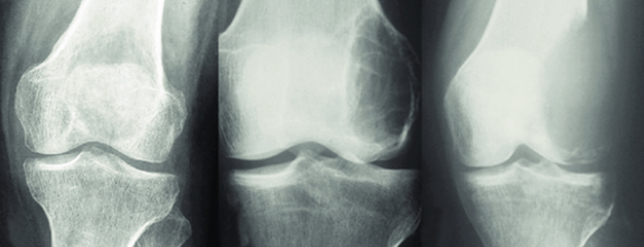

(Cited from Mavrogenis AF, Igoumenou VG, Megaloikonomos PD, Panagopoulos GN, Papagelopoulos PJ & Soucacos PN (2017) Giant cell tumor of bone revisited. SICOT J, 3, 54)

Campanacci stage is most often used for stage classification of giant cell tumor of bone and is defined as follows. Stage I tumor has a well marginated border of a thin rim of mature bone and the cortex is intact or slightly thinned but not deformed. Stage II tumor has relatively well-defined margins but no radio paque rim; the combined cortex and rim of reactive hone is rather thin and moderately expanded but still present. Stage III tumor designats a tumor with fuzzy borders, suggesting a rapid and possibly permeative growth; the tumor bulges into the soft tissues. But the soft-tissue mass does not follow the contour of the bone and is not limited by an apparent shell of reactive bone (Campanacci M, Baldini N, Boriani S, Sudanese A. Giant-cell tumor of bone. J Bone Joint Surg Am. 1987;69:106–14.).